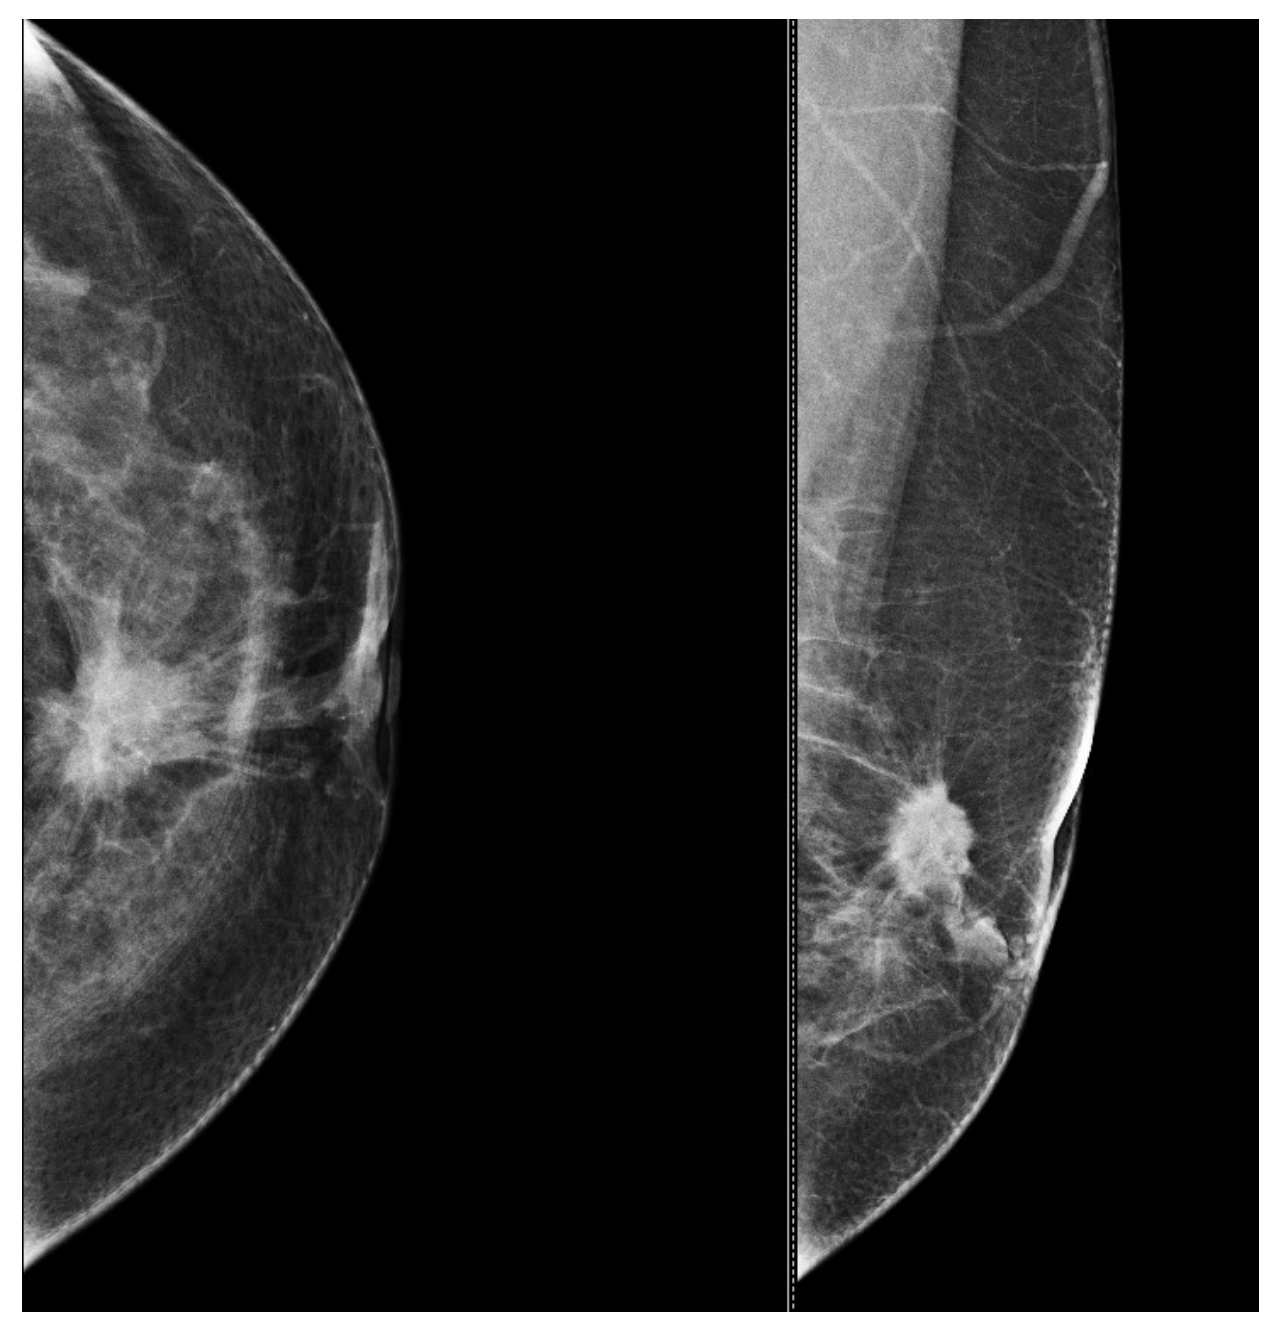

5.3. Low Ability to Detect Microcalcifications

5.4. Limited Performance in High-Risk or Dense Breast Tissue